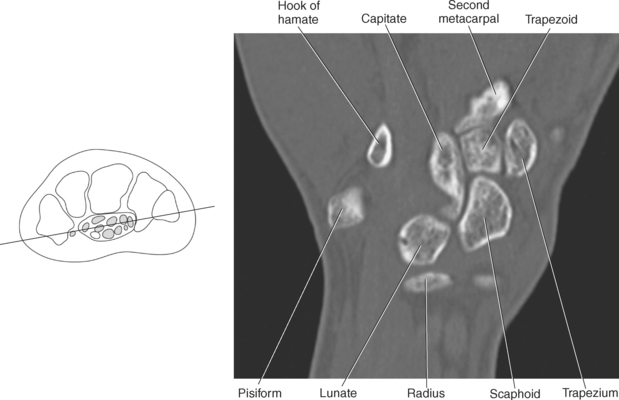

The bony anatomy of the wrist and hand consists of the distal radius and ulna, 8 carpal bones, 5 metacarpals, and 14 phalanges (Figure 9.101). Both the distal radius and ulna have a conical styloid process that acts as an attachment site for ligaments. The radial styloid process is located on the lateral surface of the radius, whereas the ulnar styloid process is located on the posteromedial side of the ulna. The carpal bones are arranged in proximal and distal rows. Located in the proximal row of carpal bones are the scaphoid (navicular), lunate (semilunar), triquetral (triquetrum), and pisiform bones. The pisiform is considered a sesamoid bone that is embedded in the tendon of the flexor carpi ulnaris. The distal row consists of the trapezium (greater multangular), trapezoid (lesser multangular), capitate (os magnum), and hamate (unciform) bones (Figures 9.102 through 9.114). The five metacarpals are small tubular bones with a proximal end (base), distal end (head), and shaft (body). The 14 phalanges that make up the fingers are short tubular bones. Like the metacarpals, each phalanx consists of a proximal (base), middle (body or diaphysis), and distal (head) portion. Each digit consists of 3 phalanges (proximal, middle, and distal), except for the thumb (first digit), which has only 2 phalanges (proximal and distal). The articulation of the phalanges of the second through fifth digits creates three interphalangeal joints: the metacarpophalangeal (MCP) joints classified as condyloid joints, proximal interphalangeal (PIP), and distal interphalangeal (DIP). The proximal and distal interphalangeal joints are classified as hinge joints (Figure 9.101). The first digit, which consists of 2 phalanges, has just two joints: the MCP joint, classified as a saddle joint, and an interphalangeal joint, classified as a hinge joint (Figure 9.101).

The joints of the wrist and hand are quite complex and consist of the following: distal radioulnar articulation, radiocarpal articulation (proximal joint of hand), midcarpal articulation (distal joint of hand), intercarpal articulations (articulations between proximal and distal carpals), carpometacarpal articulations (between carpals and metacarpals), the intermetacarpal articulations (between bases of metacarpals two through five) and the interphalangeal joints (between phalanges of each digit) (Figures 9.111 and 9.115). The distal radioulnar articulation, also called the distal radioulnar joint (DRUJ), is created when the ulnar notch of the radius moves around the articular circumference of the ulna, providing the movements of supination and pronation. The main stabilizing element of the DRUJ is an articular disk called the triangular fibrocartilage complex (TFCC). The TFCC is a fan-shaped band of fibrous tissue that originates on the medial surface of the distal radius and traverses horizontally to insert on the ulnar styloid process (Figures 9.115 and 9.116). It rotates against the distal surface of the ulnar head during pronation and supination and separates the ulna from the carpal bones. The proximal surface of the radiocarpal articulation is formed by the articular carpal surface of the radius and the TFCC, whereas the distal surface is formed by the articular surfaces of the scaphoid, lunate, and triquetrum and the interosseous ligaments connecting them (Figures 9.111 through 9.115). The midcarpal joint is formed by the articulations between the proximal and distal carpal rows (Figures 9.110 and 9.115). The articulation between the carpals within each row creates the intercarpal joints (Figures 9.111 and 9.115). The carpometacarpal joints are formed by the articulations between the carpus and the five metacarpals (Figure 9.111 and 9.115). The carpometacarpal joint of the thumb is an independent joint formed by the articular surfaces of the trapezium and first metacarpal, creating a pure saddle joint. The carpometacarpal articulations of the two to five digits are amphiarthrotic joints with little mobility (Figures 9.105 and 9.115). The intermetacarpal articulation exists between the base of the metacarpals and is joined by the palmar and dorsal metacarpal ligaments (Figure 9.115).

Numerous ligaments provide additional stability to the wrist. The extrinsic ligaments reinforce the joint cavity surrounding the carpal region and include palmar and dorsal radial carpal ligaments, the radial and ulnar collateral ligaments, and the TFCC (Figures 9.115 through 9.117). The many articulations between the carpal bones are supported by the intercarpal ligaments or intrinsic ligaments that connect the carpal bones to each other (Figure 9.115). The configuration of the intrinsic ligaments, metacarpal ligaments, and triangular fibrocartilage complex creates five different joint compartments that can be demonstrated at arthrography: (1) compartment of the first carpometacarpal articulation, (2) common carpometacarpal compartment, (3) mediocarpal compartment, (4) intermetacarpal compartment, and (5) radiocarpal compartment (Figure 9.115). The carpal tunnel is created by the concave arrangement of the carpal bones (Figure 9.103). A thick ligamentous band called the flexor retinaculum (transverse carpal ligament) stretches across the carpal tunnel to create an enclosure for the passage of tendons and the median nerve (Figures 9.118 through 9.120). The flexor retinaculum inserts medially on the pisiform and hook of the hamate and spans the wrist to insert laterally on the scaphoid and trapezium. In addition to the carpal tunnel, another tunnel called Guyon’s canal is formed where the ulnar extension of the flexor retinaculum continues over the pisiform and hamate. This creates a potential site for compression of the ulnar nerve (Figures 9.118, top, and 9.119). The extensor retinaculum (dorsal carpal ligament), located dorsally, is much thinner. It attaches medially to the ulnar styloid process, triquetrum, and pisiform and laterally to the lateral margin of the radius (Figure 9.120, left). Along its course it forms six fibroosseous tunnels for the passage of the synovial sheaths containing the extensor tendons (Figure 9.118, bottom).